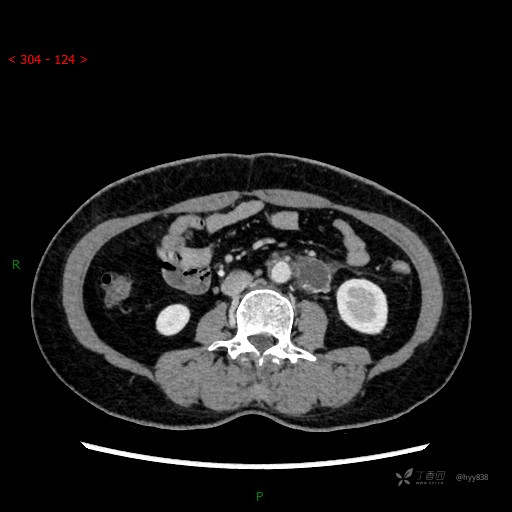

腹膜后少见疑难病例,请注重细节分析---结果公布~

增强动脉期

静脉期

CT平扫是外院的,因图像质量原因,不方便上传!